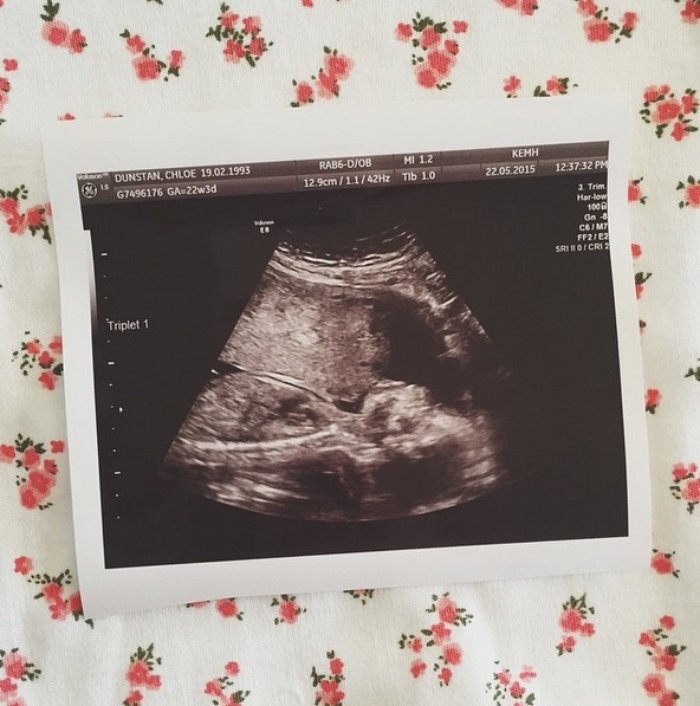

- Doktor kontrolünde yeni bir sürpriz ile karşılaşıyorlar: Üçüz çocukları olacağı ortaya çıkıyor!

Doktor kontrolünde yeni bir sürpriz ile karşılaşıyorlar: Üçüz çocukları olacağı ortaya çıkıyor!

Üçüzlerden ikisi yine erkek ama diğeri bir kız

Birkaç haftanın ardından erkeklerin kız bebeğin gelişimine izin vermedikleri ortaya çıkıyor. Bu nedenle doktorlar kızın alınmasını öneriyorlar

Ancak kızın yaşaması için erken doğum gerekiyor ama bu durumda oğlanlarında zarar görebileceği belirtiliyor

Chloe zor bir karar alıyor ve kızını feda etmeyerek 28 haftada erken doğum yapıyor!